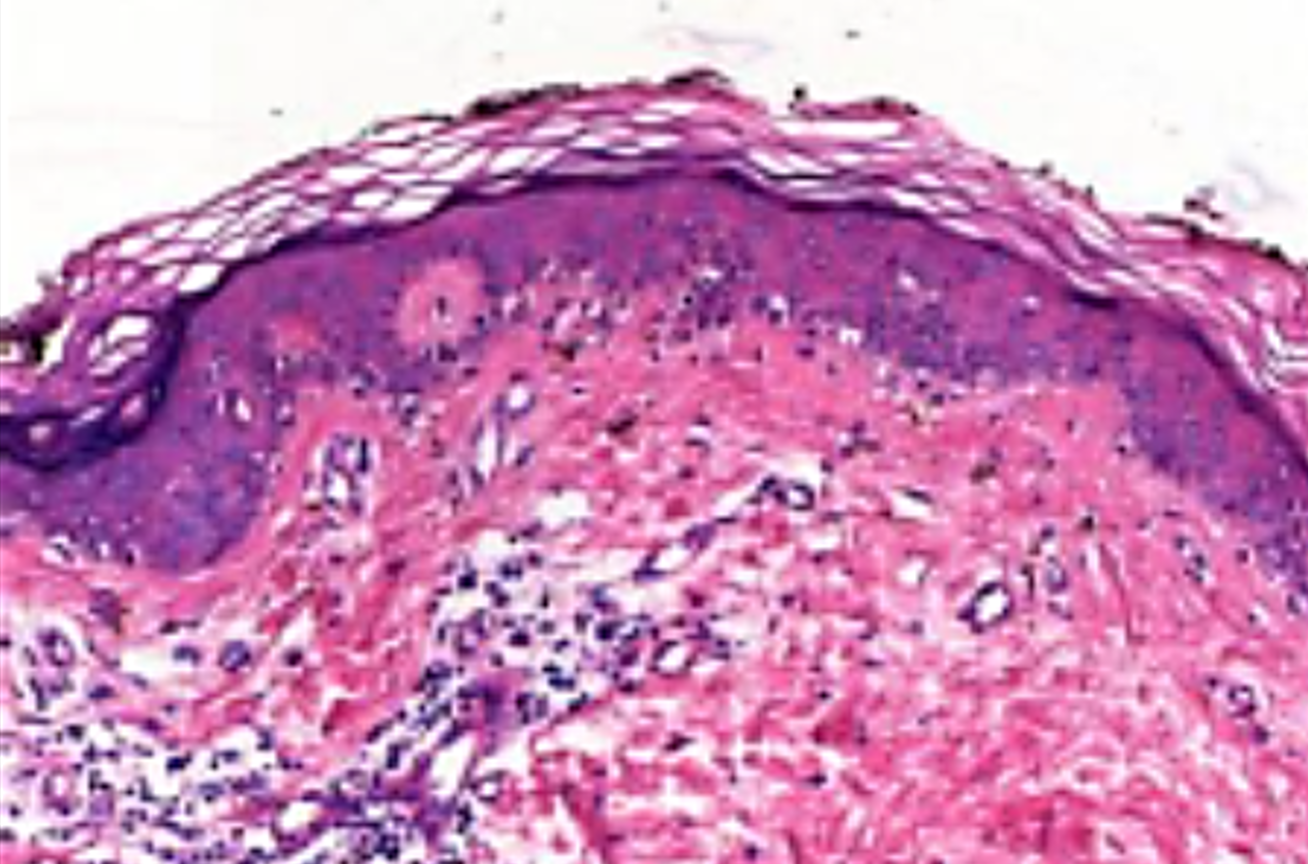

Method: We present a 62-years old male patient with hepatitis C-virus (HCV) cirrhosis and successfully downstaged to Milan criteria HCC. Orthotopic liver transplantation was performed after 6 months of surveillance and discharged uneventfully after 7 days. One month later patient developed abdominal cramps, diarrhea and cutaneous erythema. Mild leukopenia with normal liver and renal function, blood and stool samples were negative, clostridium and other pathogens were also ruled out. Abdominal CT-scan showed moderate distal ileum and colon wall edema. At colonoscopy stellate ulcers was found, biopsy was taken as well to skin lesions. Colon biopsy showed acute inflammation with severe mucosal damage and apoptosis. Skin biopsy showed interphase vacuolar dermatitis. GVHD was suspected and donor lymphocyte chimerism was positive with 5%.